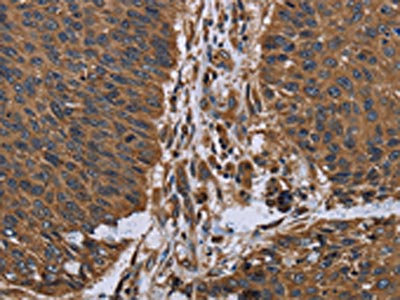

• The image on the left is immunohistochemistry of paraffin-embedded Human colon cancer tissue using CSB-PA249653(ITGA2B Antibody) at dilution 1/40, on the right is treated with fusion protein. (Original magnification: ×200)

• The image on the left is immunohistochemistry of paraffin-embedded Human lung cancer tissue using CSB-PA249653(ITGA2B Antibody) at dilution 1/40, on the right is treated with fusion protein. (Original magnification: ×200)